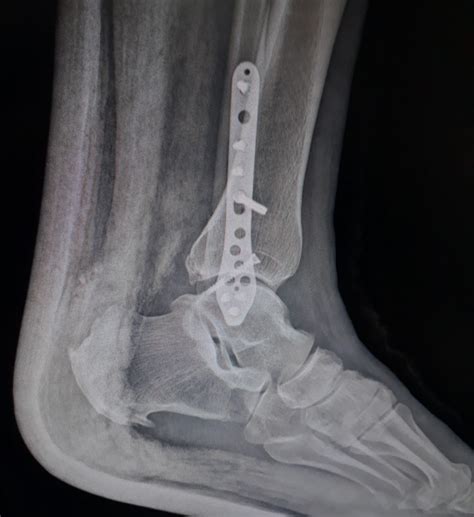

Patients Are Suing Over The Failure Of A Specific Fibula Plate